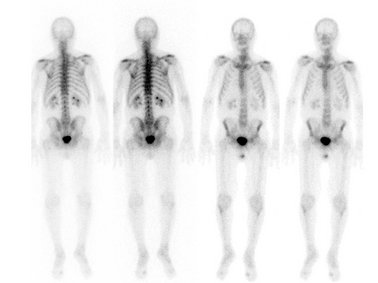

- die Skelettszintigrafie zum Ausschluss oder Nachweis von Knochenmetastasen, Rheuma, Brüchen und Entzündungen